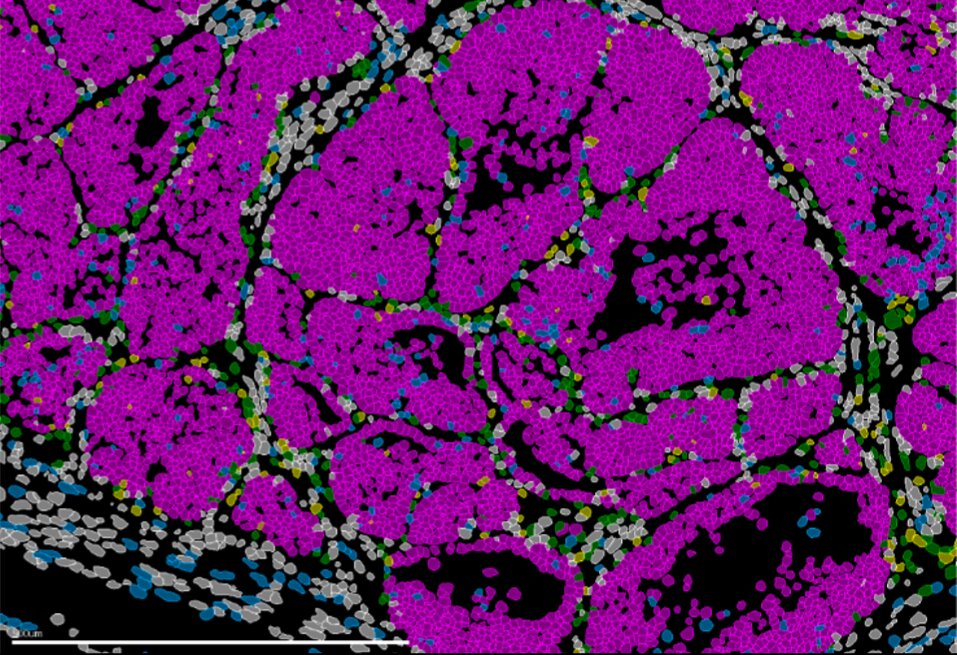

Tumor de mama en ratón con células cancerosas (rosa). IN CSIC-UMH